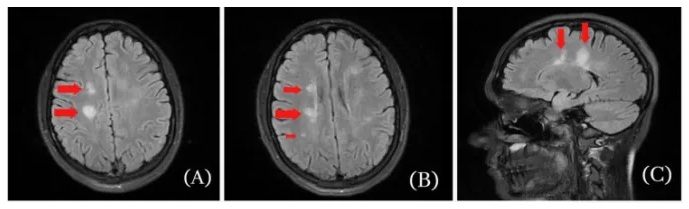

Eine 25jährige, die bereits in der Vergangenheit an Multipler Sklerose erkrankt war, wird in einem Krankenhaus vorstellig, weil es ihr seit fünf Tagen nicht mehr möglich ist, den linken Fuß zu benutzen, sie ihn nur hinterherziehen kann. Sie berichtet, dass sich ihre linken Extremitäten seit Tagen steif anfühlen und nicht belastbar sind. Die Symptome bleiben auch in den nächsten Tagen konsistent. Fünf Jahre zuvor war bei der 25jährigen Multiple Sklerose diagnostiziert, mit Hilfe von Steroiden aber vollständig zum Verschwinden gebracht worden. Dem Wiederaufflammen von Multipler Sklerose war unter anderem die Impfung mit Johnson&Johnsons Adenovirus basiertem Impfstoff vorausgegangen. Eine Kernspintomographie zeigt eine Reihe von Flüssigkeitsansammlungen im Gehirn der Patientin:

MS kommt wieder nach der

SCHLANGENGIFTimpfung, Flüssigkeitsblasen im Hirn

MS kommt wieder nach der SCHLANGENGIFTimpfung, Flüssigkeitsblasen im Hirn [2]

T2-weighted MRI images of the brain. A & B: Axial images of brain MRI demonstrating several foci of FLAIR hyperintensities (red arrows); C: Sagittal image of brain MRI showing large FLAIR in right posterior frontal lobe measuring 1.4 cm (red arrow). Quelle. Al-Midfai et al. (2022).

Multiple Sklerose ist eine Autoimmunerkrankung, die das zentrale Nervensystem schädigt. Das Wiederaufflammen von Multipler Sklerose bei der 25jährigen wurde von einer akuten, entzündlichen demyelisierenden Reaktion im zentralen Nervensystem begleitet, also einer Zerstörung der Myelinscheide von Nervenzellen. Im vorliegenden Fall ist das Wiederaufflammen von Multipler Sklerose nach Ansicht der Autoren auf die vorausgehende Impfung mit dem Adenovirus-basierten Impfstoff von Johnson&Johnson zurückzuführen.